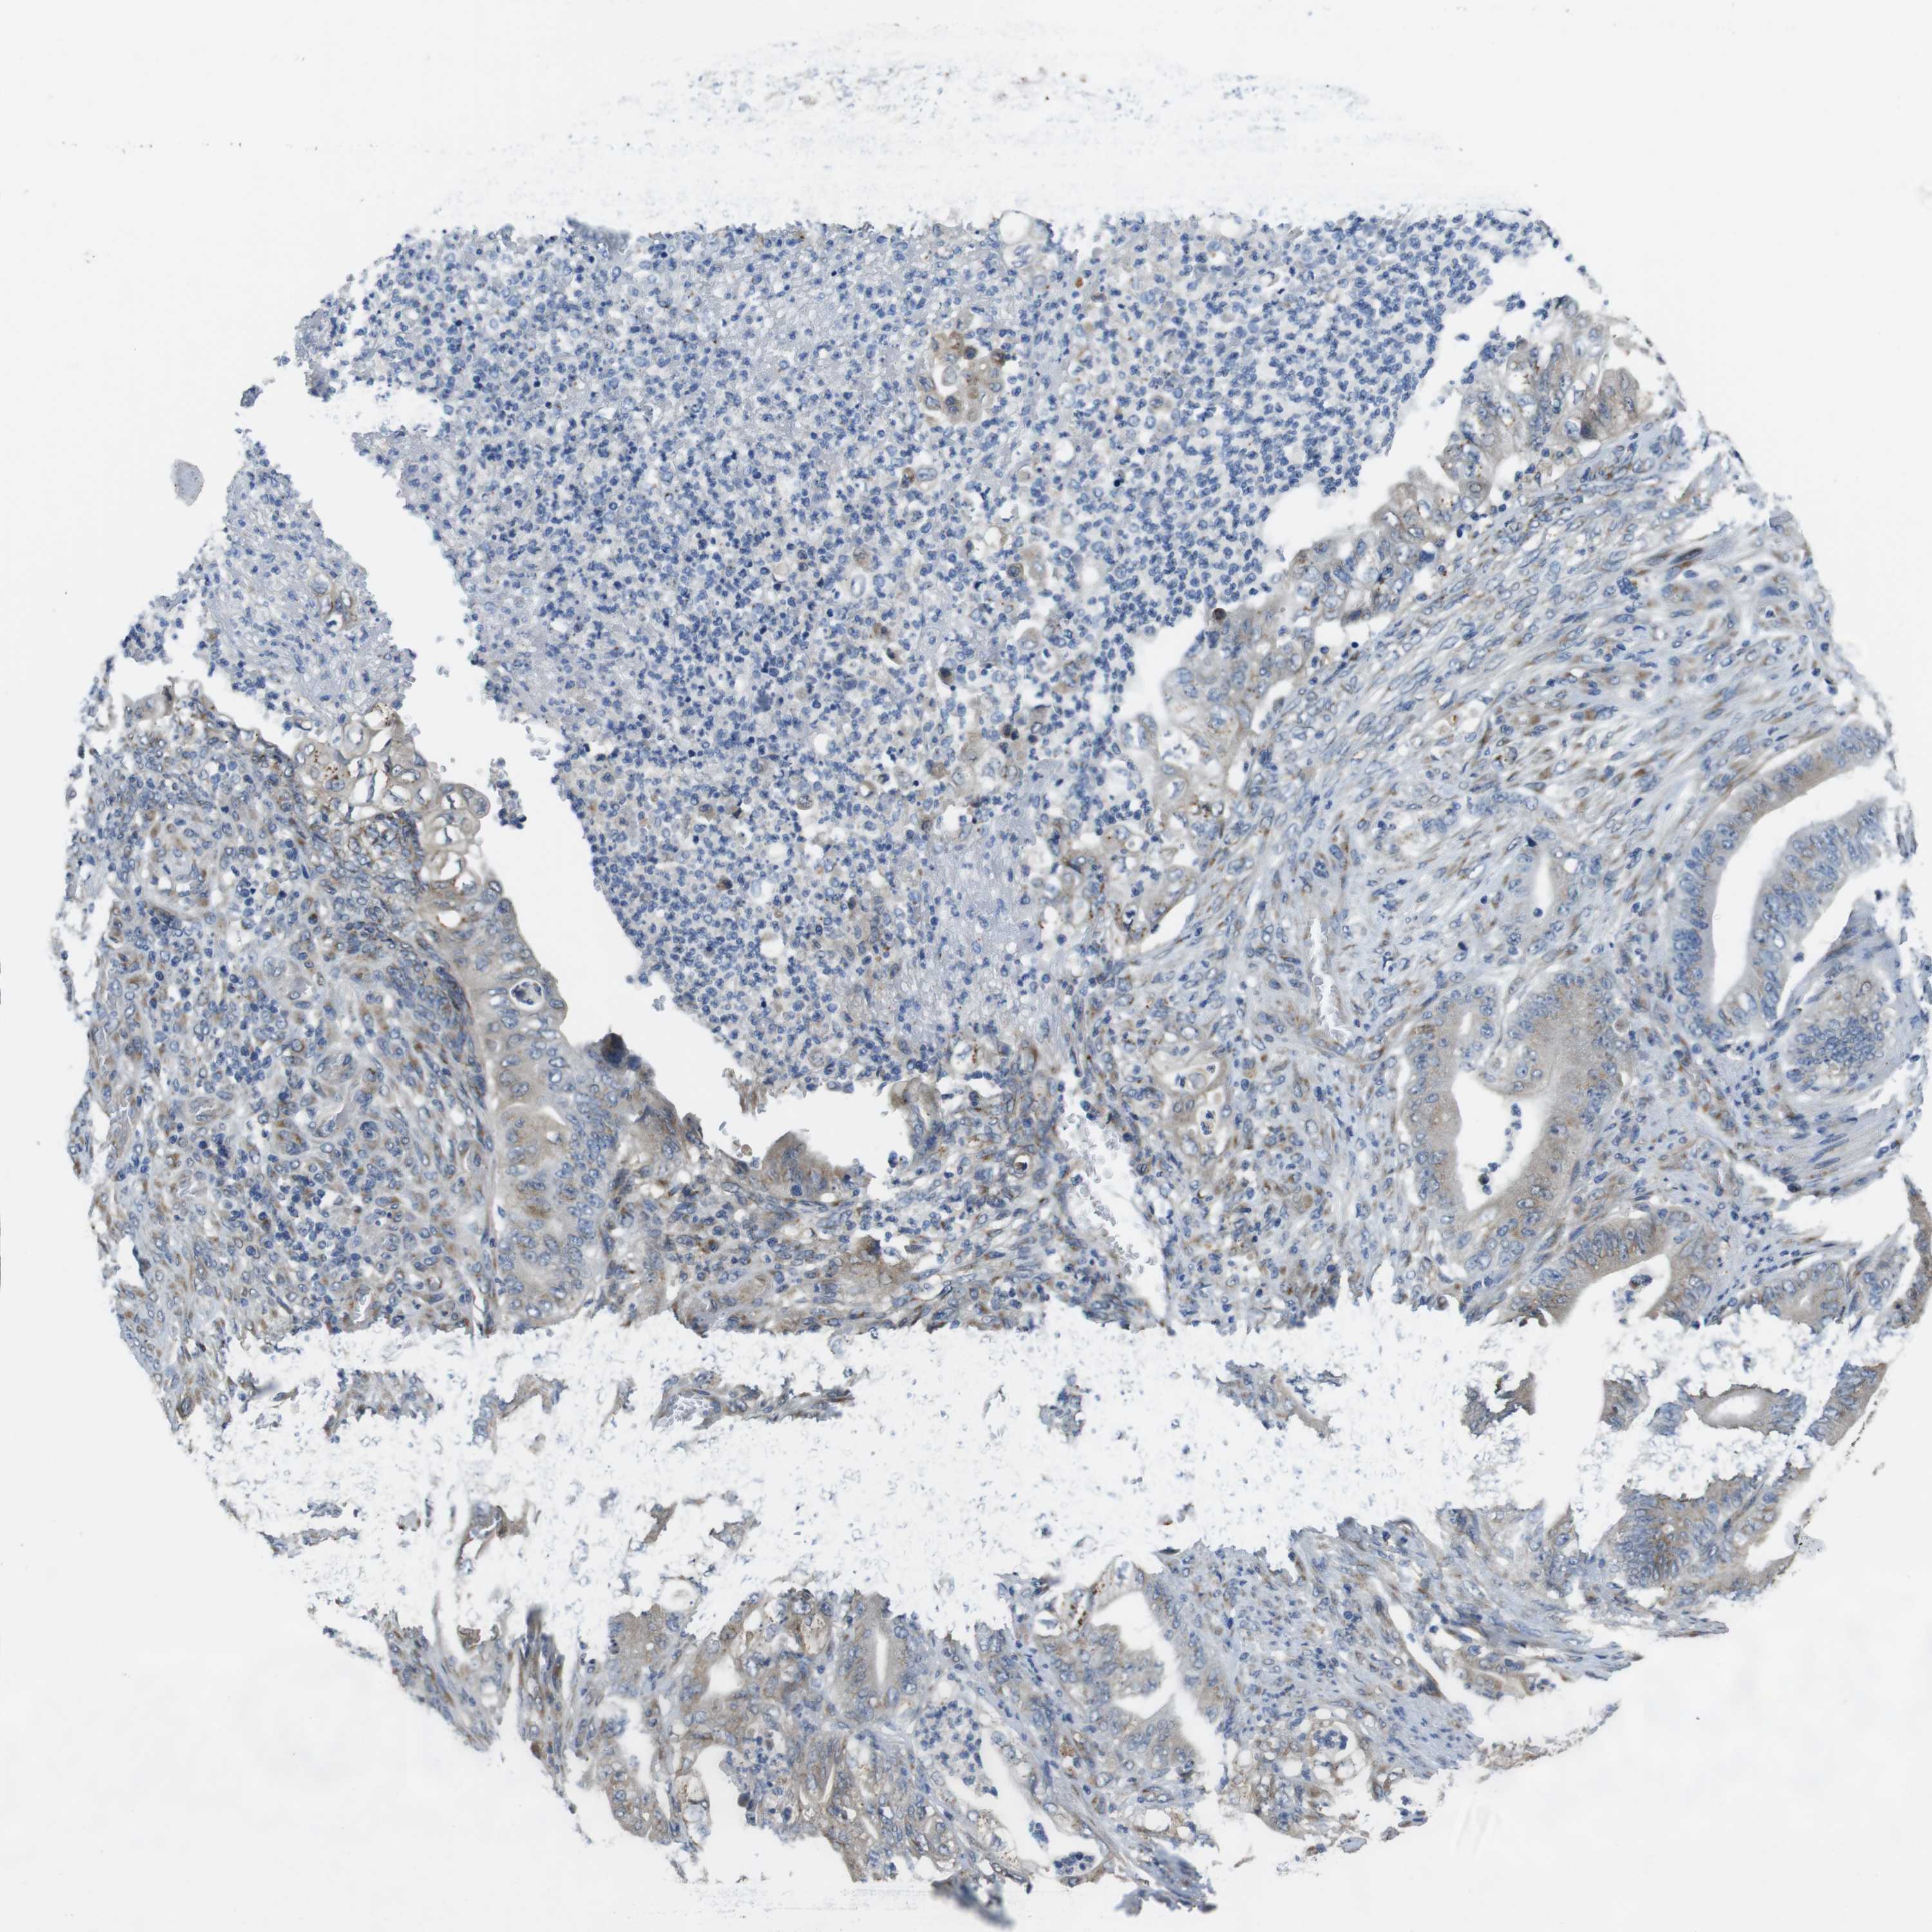

STOMACH CANCER - Protein expressioni

A mouse-over function shows sample information and annotation data. Click on an image to view it in a full screen mode. Samples can be filtered based on level of antibody staining by selecting one or several of the following categories: high, medium, low and not detected. The assay and annotation is described here.

Note that samples used for immunohistochemistry by the Human Protein Atlas do not correspond to samples in the TCGA dataset.

Antibody stainingi

Antibody staining in the annotated cell types in the current human tissue is reported as not detected, low, medium, or high, based on conventional immunohistochemistry profiling in selected tissues. This score is based on the combination of the staining intensity and fraction of stained cells.

Each image is clickable and will lead to virtual microscopy that enables deeper exploration of all samples and also displays staining intensity scores, fraction scores and subcellular localization as well as patient and tissue information for each sample.

Antibody HPA059131

Antibody CAB009936

Staining

High

Medium

Low

Not detected

Intensity

Strong

Moderate

Weak

Negative

Quantity

>75%

75%-25%

<25%

None

Location

Nuclear

Cytoplasmic/membranous

Cytoplasmic/membranous,nuclear

Adenocarcinoma, NOS

Adenocarcinoma, High grade